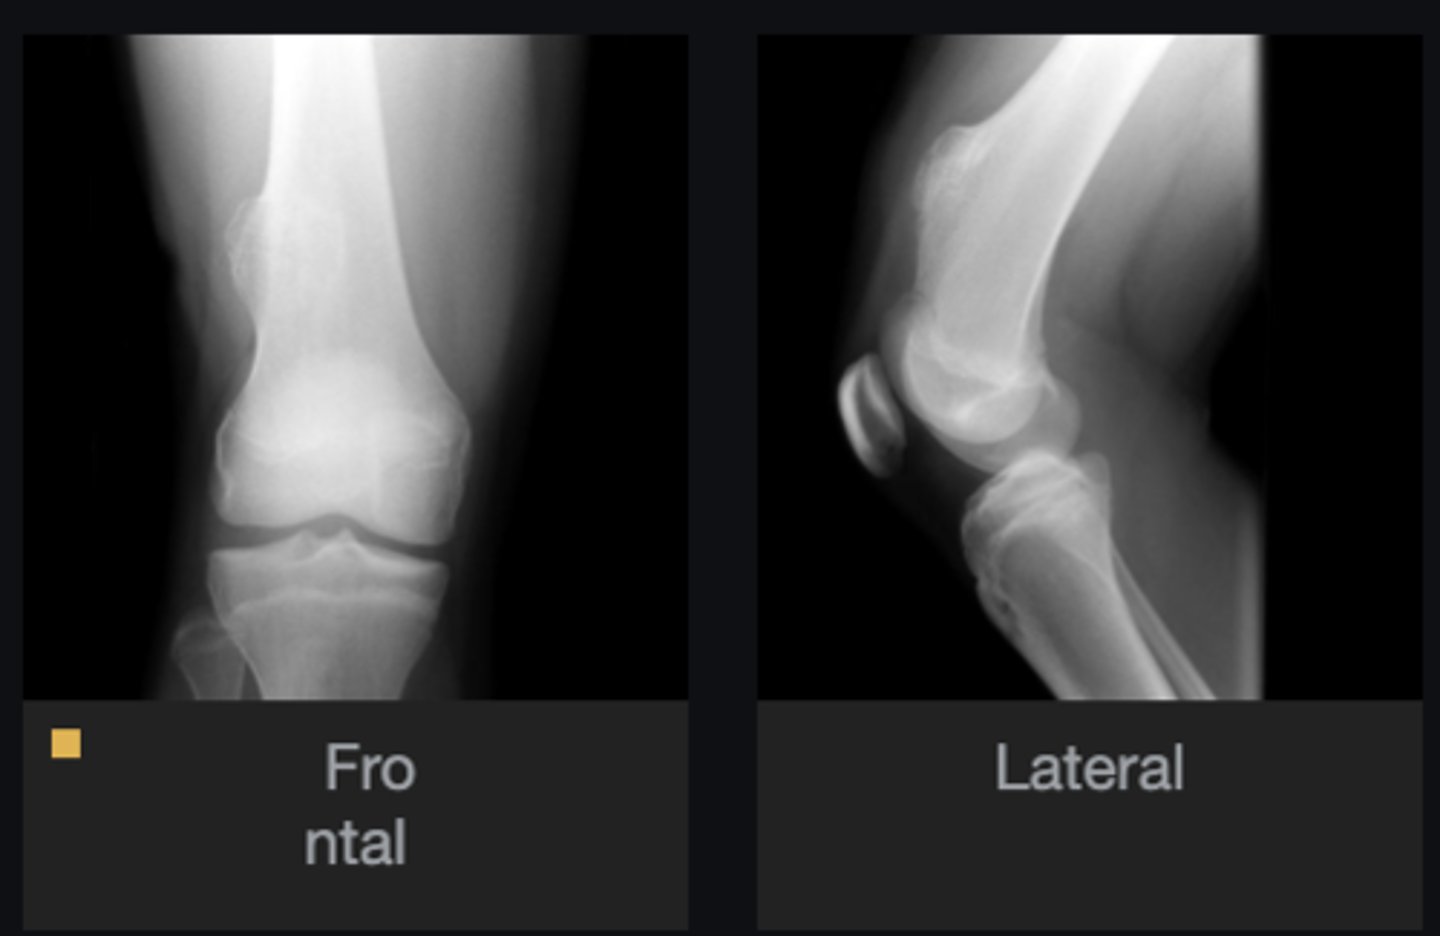

- Solitary

- Eccentric

- Geographic

- Multiloculated

- Fibrous matrix

- Small

- Cortical thinning

- Sclerotic border

Describe the lesion

<p>Describe the lesion</p>

Non-Ossifying Fibroma

Diagnosis?

Nothing

Next step?

<p>Next step?</p>

- Anterolateral distal tibia

- Metaphysis

- Septation

<p>Diagnosis?</p>

- Look for fracture

- Refer to orthopedist